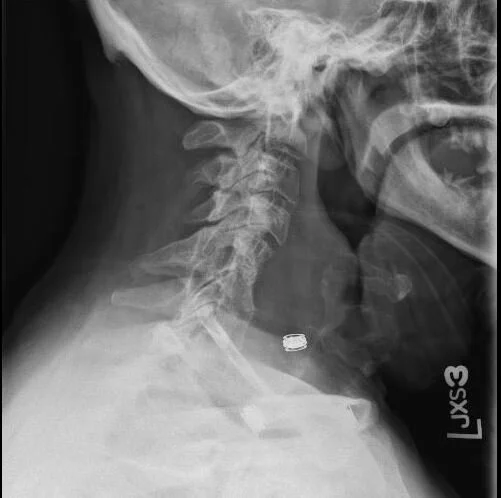

A 49 y.o. farmer with DM, COPD, presents with difficulty swallowing x three weeks.

What do you notice on his plain film?

What is the differential for this bony erosion?

Our  patient had disseminated blastomycosis.  Blastomycosis is a chronic granulomatous mycosis of humans and animals (primarily dogs). In humans pulmonary cutaneous and disseminated forms occur. It was first described as a cutaneous disease in 1894 by Thomas Gilchrist  who identified the etiologic agent as a fungus. The cases most frequently occur in the Mississippi valley .

Blastomycosis enters the body through the lungs usually causing pneumonia. It converts from a mold form to a yeast form in the lungs. 3-15 weeks after inhaling the conidia of the fungus fever, cough, body aches or chest pain may develop. 50% of people are asymptomatic. When Blastomycosis disseminates, often the pulmonary lesion has healed. disseminated blastomycosis often causes osteomyelitis or skin lesions.  In 5% of cases it may cause CNS involvement with meningitis , intracranial abscesses or spinal epidural abscesses. Lymphocytic pleocytosis is noted in the CSF but the organism is difficult to grow from culture and a brain biopsy is recommended especially if there is meningeal enhancement on MRI. Blastomycosis meningitis can appear very similar to tuberculous meningitis and is often treated with antituberculosis drugs before the diagnosis is made.

Our patient elected not to have surgery for neck stabilization because he did not want to be out of work.  He is currently taking one year of ambisome.